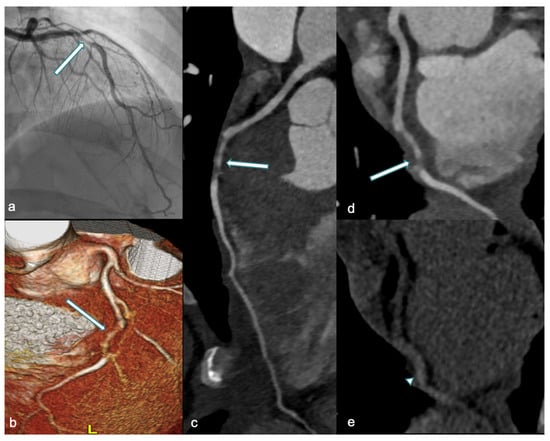

5.1. CCTA: Roles and Findings

Over the last years, the role of CCTA in assessing acute SCAD has been investigated, with several studies highlighting the utility of this imaging modality [86,87]. Pergola et al. recommend utilization of CCTA in acute settings for stable patients with a high suspicion of SCAD who do not exhibit high-risk features (i.e., ST elevation, progressive increases in serum troponin, or worsening chest pain) [84]. Moreover, the safety of CCTA makes this technique the preferred modality for follow-up in both asymptomatic and symptomatic patients. In a recent blinded study, the accuracy of CCTA in assessing coronary dissection healing was evaluated, with sensitivity and specificity found to be 72% and 53.8%, respectively. Additionally, the authors estimated that the optimal timing for CCTA to assess dissection healing was 80 days [88]. Roura and colleagues explored the feasibility of non-invasive follow-up in 34 SCAD patients, concluding that CCTA is an excellent tool that allows assessment and confirmation of vessel wall healing in most patients, particularly those who did not undergo percutaneous coronary intervention (PCI) [89]. The CCTA appearance of SCAD includes both primary and secondary findings (Figure 5), as reported in Table 2 [90].

Figure 5.

A 36-year-old woman at week 36 of pregnancy presented with chest pain and anterior ST-segment elevation on ECG. Urgent ICA (a) and CCTA performed one week later (3D-VR, (b) and curved-MPR, (c,d)) revealed a tapered luminal stenosis in the mid-LAD (white arrow), consistent with mid-LAD dissection. In (e), unenhanced CT shows high-density thickening of the mid-LAD wall, suggestive of IMH (arrowhead). ICA: invasive coronary angiography; CCTA: coronary computed tomography angiography; 3D-VR: three-dimensional volume rendering; MPR: multiplanar reconstruction; LAD: left anterior descending artery; and IMH: intramural hematoma.

The most common artery involved is the left anterior descending (LAD), followed by the left circumflex artery (LCX) and the right coronary artery (RCA), with multivessel disease occurring in 10%–15% of cases [91]. Despite its benefits, CCTA has certain limitations. Its accuracy is reduced for small vessels, as distal coronary arteries or side branches may be missed due to limitations in spatial and temporal resolution. Another pitfall involves motion artifacts, which can blur the vessel and the adjacent perivascular fat, mimicking a dissection flap or stenosis and potentially leading to misinterpretation as SCAD [85].